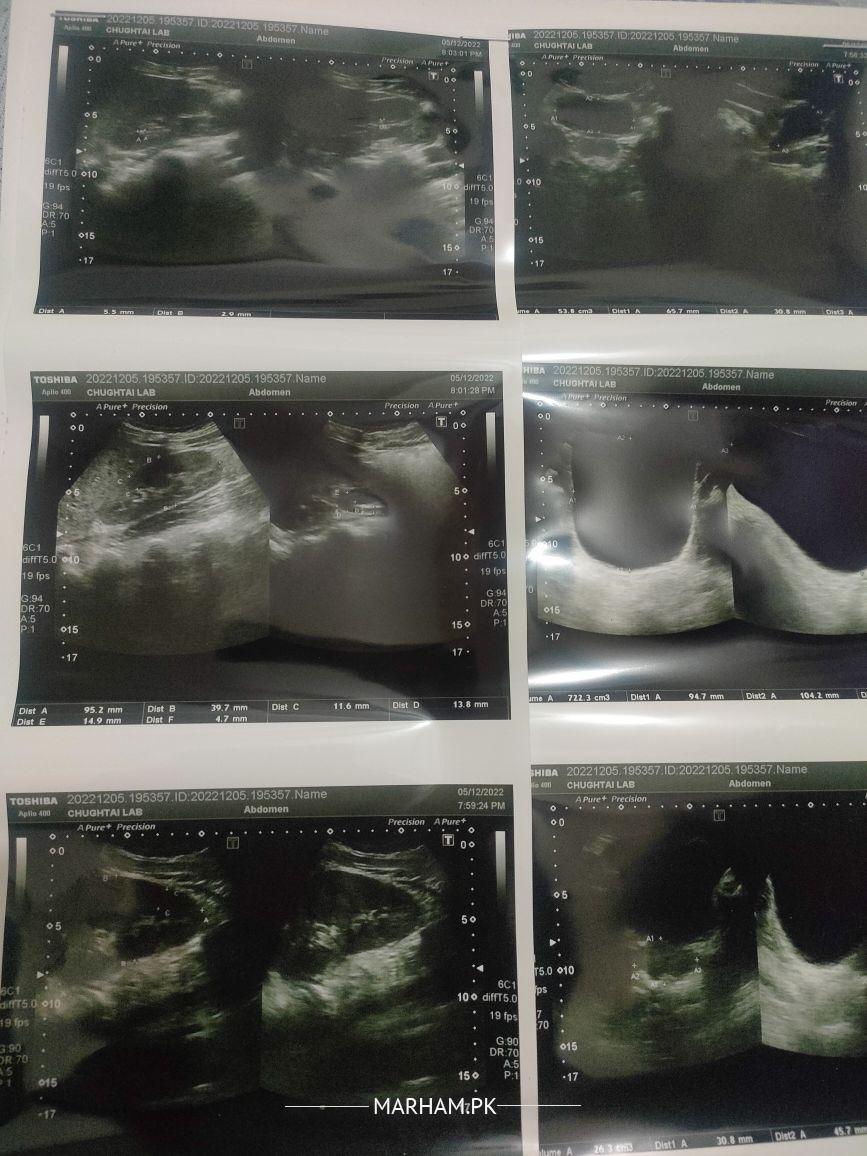

Asking For Self, Male 22, Lahore

Ya mere kidney ultrasound ki report ha koi report ka bare ma bata sakta ha ka kiya issue haii Jazakallah

Right kidney me small stones hain jo thori si medicine se nikl jain gy inshallah ap pareshan na hon detail bat kr lain kindly book appointment with me buhat jldi furq parh Jay ga inshallah

right side ka ureter (gurdy wali nali) ki swelling hy.. iski wja ureter ka stone hta hy..

ureter ka stone ultrasound pr nai ata.. usk leye ct scan krwana prta hy..apna ct scan krwaein

CT SCAN KUB PLAIN

book appointment via marham....ap ka right kidney mae stone hae

Cap Rovatinex 1+1+1

useplenty water

and repeat U/S after 1 month.